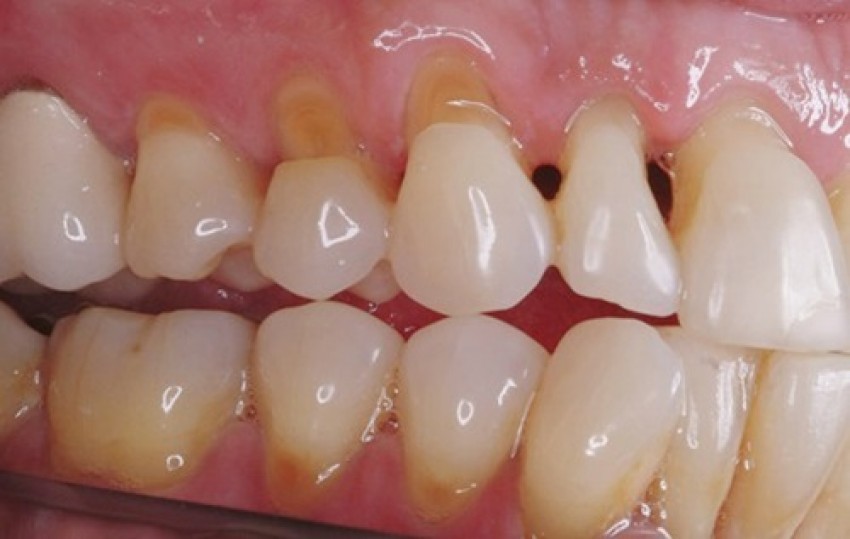

Mòn cổ răng là một rãnh sâu, lõm vào hình chữ V ở mặt ngoài răng ở sát viền lợi, hay gặp ở các răng cối nhỏ (răng số 4 và 5), răng số 6 và các răng cửa. Triệu chứng thường gặp của bệnh lý này chính là tình trạng ê buốt răng khi ăn các thức ăn nóng lạnh hoặc chua ngọt.

Răng cũng bị ê nhức khi bạn đánh răng hoặc sử dụng nước súc miệng, cũng có trường hợp răng bị mòn trở nặng hơn có thể gây viêm tủy, viêm xung quanh chóp răng. Mòn cổ thường xảy ra ở răng cửa, răng nanh và răng hàm cối nhỏ. Ban đầu, dấu hiệu của mòn cổ răng chỉ là một rãnh nhỏ dưới gần chân răng khiến bệnh nhân không để ý. Dần dần, rãnh mòn phát triển gây đau nhức, ê buốt và trong trường hợp nặng có thể gãy ngang thân.

Biểu hiện dễ nhận biết là cổ răng bị khuyết, lõm sâu có hình chữ V (còn gọi là lõm hình chêm), hay gặp nhất ở mặt ngoài cổ răng hàm nhỏ hàm trên, ngoài ra còn thấy ở răng cửa và răng hàm lớn. Đôi khi nó được phát hiện khi răng xuất hiện hiện tượng nhạy cảm với nhiệt độ (ê buốt răng khi ăn các thức ăn nóng lạnh) hoặc thức ăn ngọt, chua.